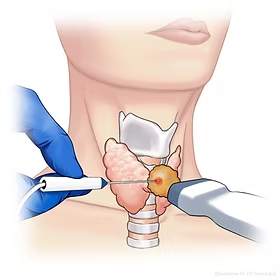

Thyroid Nodule Ablation

After completing my medical training, residency and advanced fellowship in Vascular & Interventional Radiology from the best institutes in the country, I’ve dedicated my career to offering precise, minimally invasive treatments for wide variety of complex conditions like uterine fibroids, thyroid nodules, varicose veins, prostate enlargement, knee joint pains, liver diseases, cancer and many more. Although technology enables precision in Interventional Radiology, but it is compassion, empathy, and ethics that bring meaning to medicine and guide every decision I make in my patient treatment.